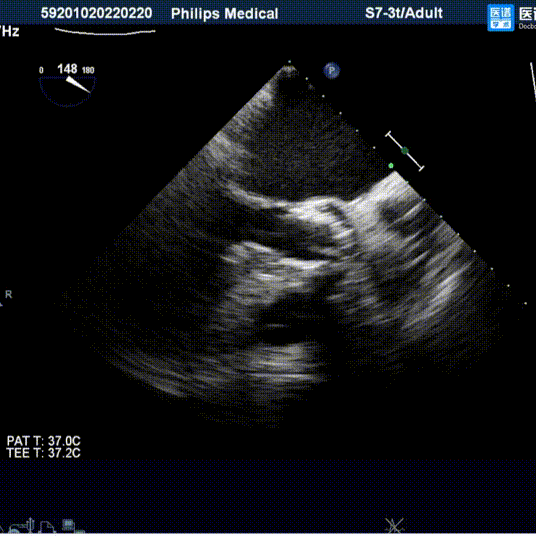

男,78岁,因“发作性胸痛10余年,加重2月”入院。超声检查主动脉瓣Vmax = 4.1m/s ,PGmain=41 mmHg,EF值60%,诊断为重度主动脉瓣狭窄。

超声下评估植入深度

植入后超声评估: